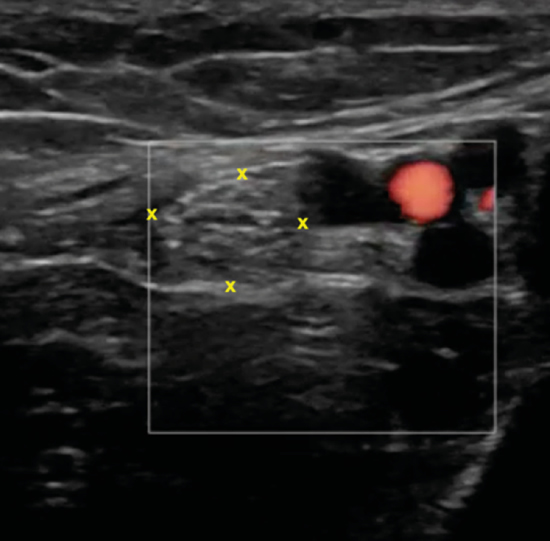

Figura 6. Túnel tibiocalcáneo. El examen en eje corto, bajo la fascia crural (*) y de anterior a posterior, muestra el tendón tibial posterior (TP), el tendón flexor largo de los dedos (FCD) aún con fibras musculares, y el músculo flexor largo del primer dedo (FLD). Entre estas dos estructuras se encuentra el haz neurovascular que está formado por las venas (V), la arteria (A) tibial posterior y por el nervio tibial (rodeado por X).

El nervio tibial tiene forma más o menos redondeada, patrón fibrilar con zonas punteadas anecogénicas e hiperecogénicas que corresponden a los haces nerviosos y al tejido conectivo de sostén, la típica imagen denominada de “sal y pimienta”, y sección transversal entre 10 mm26 y 12,7 mm27 a nivel del maléolo tibial (Figura 7).

Figura 7. Examen en eje corto del nervio tibial (x) posterior adyacente a los vasos tibiales posteriores.